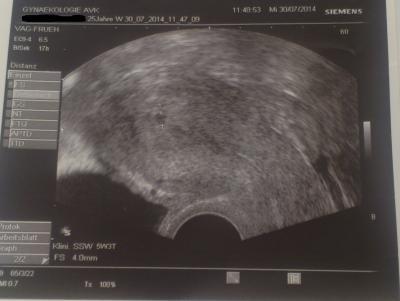

jetzt bin ich ssw 5+4 und man sah bisher auf dem Ultraschall einen 4,5mm kleinen süßen punkt also die fruchthülle mehr nicht

sitzt aber im Uterus das ist ja positiv